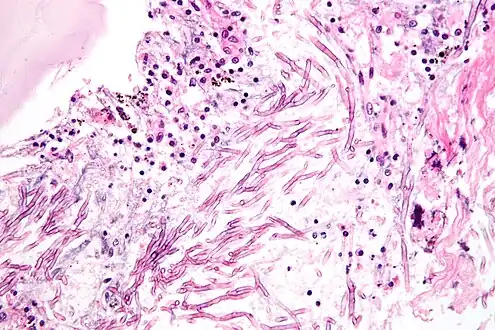

A. fumigatus (the most common species) infections are primary pulmonary infections and can potentially become a rapidly necrotizing pneumonia with a potential to disseminate. The organism can be differentiated from other common mold infections based on the fact that it takes on a mold form both in the environment and in the host (unlike Candida albicans which is a dimorphic mold in the environment and a yeast in the body).

Aspergillosis

Aspergillosis is the group of diseases caused by Aspergillus. The most common species among paranasal sinus infections associated with aspergillosis is A. fumigatus.[28] The symptoms include fever, cough, chest pain, or breathlessness, which also occur in many other illnesses, so diagnosis can be difficult. Usually, only patients with already weakened immune systems or who suffer other lung conditions are susceptible.

In humans, the major forms of disease are:[29][30]

- Acute invasive aspergillosis, a form that grows into surrounding tissue, more common in those with weakened immune systems such as AIDS or chemotherapy patients

- Allergic bronchopulmonary aspergillosis, which affects patients with respiratory diseases such as asthma, cystic fibrosis, and sinusitis

- Aspergilloma, a "fungus ball" that can form within cavities such as the lung

- Disseminated invasive aspergillosis, an infection spread widely through the body

Most people inhale Aspergillus into their lungs everyday,[32] but generally only the immuno-compromised become sick with Aspergillosis.[32]

Pulmonary aspergillosis